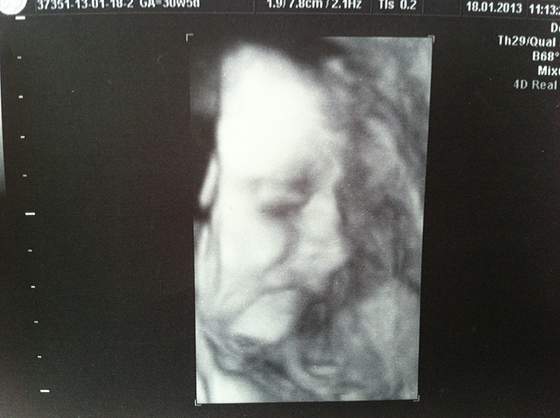

Zaraz mam przed oczami filmy z "alienami" w roli głównej. Nie mniej fajne jest to, że dzięki nim można tak dokładnie zbadać dzieciątko.